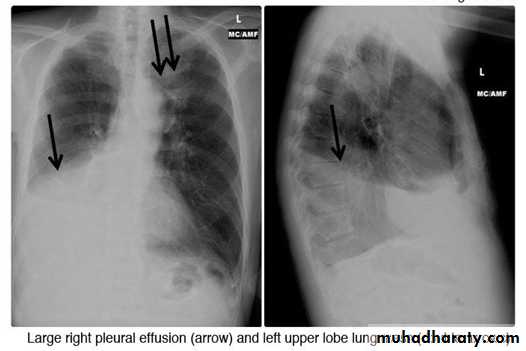

- (CXR) :The classical appearance of pleural fluid on the erect PA chest film is of a curved shadow at the lung base, blunting the costophrenic angle and ascending towards the axilla

Fluid appears to track up the lateral chest wall.

Around 200 mL of fluid is required to be detectable on a PA chest X-ray, but smaller effusions can be identified by ultrasound or CT.

Pleural fluid localised below the lower lobe ('subpulmonary effusion') simulates an elevated hemidiaphragm.

Fluid localised within an oblique fissure may produce a rounded opacity, simulating a tumour.